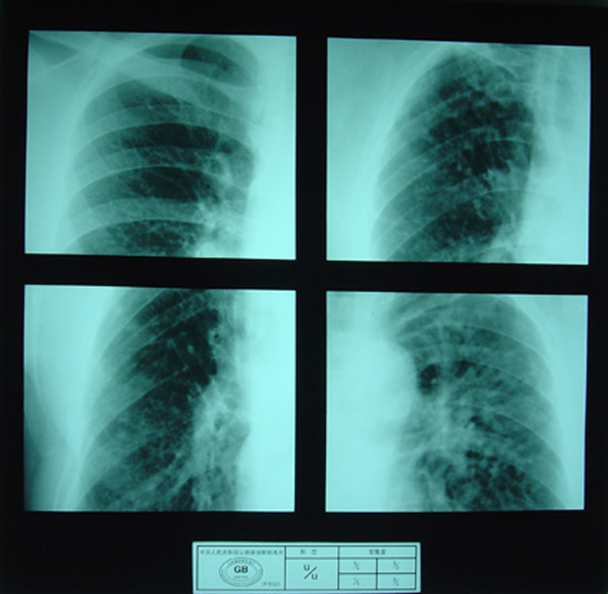

(2)X射线胸片表现:矽肺X射线胸片影像是肺组织矽肺病理形态在X射线胸片的反映,是“形”和“影”的关系,与肺内粉尘蓄积、肺组织纤维化的病变程度有一定相关关系,但由于多种原因的影响,并非完全一致。这种X射线胸片改变表现为X射线通过病变组织和正常组织对X射线吸收率的变化,呈现发“白”的圆形或不规则形小阴影,作为矽肺诊断依据。X射线胸片上其他影像,如肺门变化、肺气肿、肺纹理和胸膜变化,对矽肺诊断也有参考价值。在X射线胸片上,肺野内直径或宽度不超过10mm的阴影。小阴影按其形成分为圆形和不规则形两类。

3)大阴影:在X射线胸片上,肺野内直径或宽度超过10mm的阴影,为晚期矽肺的重要X射线表现,形状有长条形、圆形、椭圆形、或不规则形,病理基础是团块状纤维化。大阴影的发展可由圆形小阴影增多、聚集,或不规则小阴影增粗、靠拢、重叠形成;多在两肺上区出现,逐渐融合成边缘较清楚、密度均匀一致的大阴影,常对称,形态多样,呈八字形等,也有先在一侧出现;大阴影周围一般有肺气肿带的X射线表现。

大阴影

4)胸膜变化:胸膜粘连增厚,先在肺底部出现,可见肋膈角变钝或消失;晚期膈面粗糙,由于肺纤维组织收缩和膈胸膜粘连,呈“天幕状”阴影。

5)肺气肿:多为弥漫性、局限性、灶周性和泡性肺气肿,严重者可见肺大泡。

6)肺门和肺纹理变化:早期肺门阴影扩大,密度增高,边缘模糊不清,有时可见淋巴结增大,包膜下钙质沉着呈蛋壳样钙化,肺纹理增多或增粗变形;晚期肺门上举外移,肺纹理减少或消失。

尘肺叁期

尘肺叁期

尘肺叁期